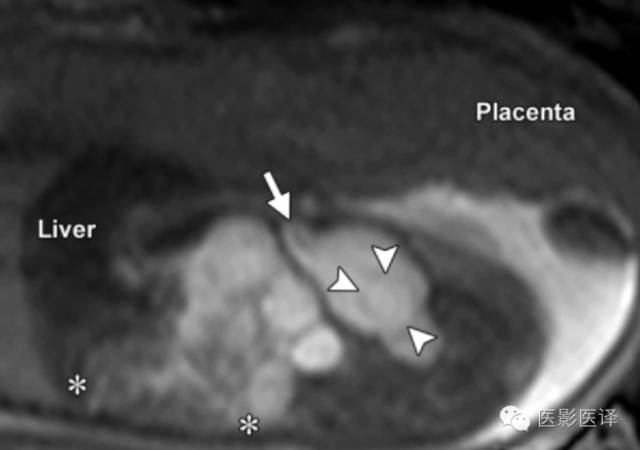

因母亲体型、胎儿位置或羊水过少而声学评价受限的病例,MR成像就很有帮助了(图8)。MR成像也可用于确认女性生殖器官和正常胃肠道及泌尿生殖道,这些是诊断胎儿卵巢囊肿所必须的。快速T2WIMR成像序列有助于显示解剖,TIWI MR成像显示胎粪为高信号,这能显示结肠走向并确认直肠。

图8MR图像可清晰显示胎儿解剖。(a)稳态进动MR图像矢状位显示一囊肿内伴多发分隔(黑箭),该囊肿位于肝脏下缘、肾脏(K)前缘。可见脐静脉(uv;白箭)进入肝左叶。(b,c)稳态进动MR图像横断位显示胎儿子宫(图b中箭头所示)位于膀胱(B)后方,提示女性内生殖器,阴唇(图c中箭头所示),提示女性外生殖器。证实了女性生殖器存在也就可以支持卵巢囊肿的诊断;若显示为男性生殖器则可以将卵巢囊肿从鉴别诊断中排除。

胆管囊肿是由于胆胰管连接部畸形所致的肝外或肝内胆管扩张。表现为右肝下间隙上份的单房囊肿,同肝被膜相邻。如果囊性肿物与入肝的扩张胆管直接相通,则可确诊胆管囊肿(图18)。磁共振成像能够更好的评价囊肿与扩张胆管、胆囊和肝脏的关系。如胆管囊肿没有切除,则产后并发症包括恶变、胆管炎和胰腺炎。胆道受累可以排除卵巢囊肿。

图18.胆管囊肿。(a)孕32周超声斜冠状位显示一个卵圆形囊性结构,有分支从肝实质进入该囊性结构。分支位于肝内,囊肿与肝实质关系密切,与胃壁有清楚的分界。(b)插图显示一个胆管囊肿的典型位置与解剖关系。